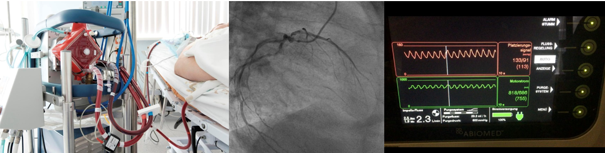

Our research group focuses on coronary vascular disease and critical care medicine, particularly in the areas of cardiogenic shock, hemodynamics, endothelial function, and microcirculation. Professor Jung and his team employ a multidisciplinary approach encompassing basic, translational, and clinical research to develop innovative treatment strategies for critically ill patients.

In the last decades, advantages in the Cathlab and intensive care medicine are promising. Notable aspects of his work are his involvement in the European project INDICATE indicate-europe.eu ("Connecting Intensive Care Data Across Europe"), which aims to enhance intensive care by linking and analyzing health data across borders by using artificial intelligence models, or, the research groups´ participation and own conduction of (international) multicenter studies. Moreover, our research group aims at improving outcome assessment and risk stratification of critically ill patients. In this regard, we assess novel diagnostic tools, such as retinal microcirculation analyses or tonometry, to strengthen prognostic validity.

Professor Jung's contributions extend to various clinical applications, including advanced diagnostic techniques like Fractional Flow Reserve (FFR), Instantaneous Wave-Free Ratio (iFR), and intravascular imaging (i.e., IVUS and OCT). These methodologies are integral to the management of chronic coronary artery disease and acute coronary syndromes.